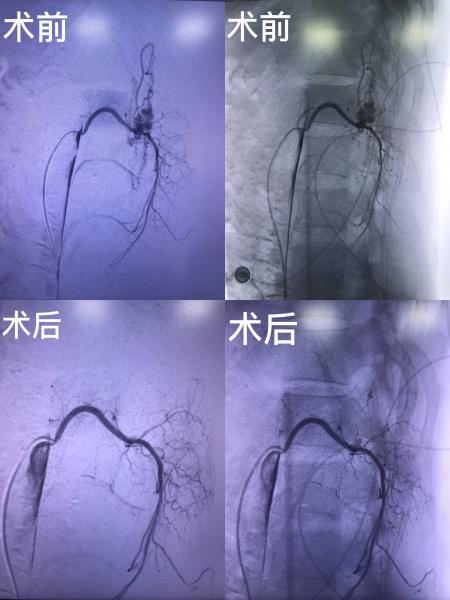

治疗前后造影情况对比,瘘口与扩张静脉已不显影